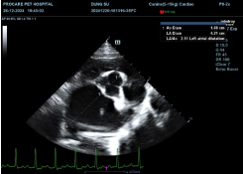

Fig. 3. Measurement of the LA/Ao ratio in dogs with MMVD

The LA/Ao ratio increased significantly across stages (p < 0.001), from 1.38 ± 0.10 (B1) to 1.76 ± 0.08 (B2) and 2.18 ± 0.17 (C). According to the EPIC trial (Boswood et al., 2016), LA/Ao ≥ 1.6 defines stage B2. The high LA/Ao values in stage C reflect severe left atrial enlargement due to chronic mitral regurgitation and are closely associated with the risk of congestive heart failure and survival time (Boswood et al., 2016).

Echocardiographic evaluation: The thoracic area of dogs was clipped, gently disinfected, and positioned in lateral recumbency with light restraint before examination. Transthoracic echocardiography was performed using 2D, M-mode, and color Doppler techniques. Two-dimensional imaging was used to detect thickening or prolapse of the mitral valve in standard views (Menciotti & Borgarelli, 2017). M-mode was used to measure LVIDD and LVIDS, which were then normalized to body weight to calculate LVIDDN and LVIDSN according to Cornell et al. (2004), and fractional shortening (FS) was calculated. Color Doppler was used to detect and assess mitral regurgitation. The LA/Ao ratio was used to evaluate left atrial enlargement, with values > 1.6 indicating progressive MMVD (Keene et al., 2019). Additional parameters included ejection fraction (EF; normal 50–70%) and the E/A ratio to assess systolic and diastolic function (Oyama et al., 2009).

Both LVIDd and LVIDs increased significantly (p < 0.001) from B1 to C, indicating progressive eccentric hypertrophy and left ventricular remodelling. These findings are consistent with Franco et al. (2011), who showed that these indices are sensitive markers of disease progression and treatment response. Thus, imaging parameters, especially VHS, LA/Ao, and LVIDd/LVIDs, are highly valuable for staging and prognostication of MMVD. Thresholds such as VHS > 10.5–11, LA/Ao > 1.6–2.0, and LVIDd > 2.0 help distinguish compensated from decompensated stages. Although FS remains within normal limits in early stages, structural changes of the cardiac chambers occur early, indicating that assessment of cardiac morphology should be prioritized over systolic function alone in monitoring MMVD.